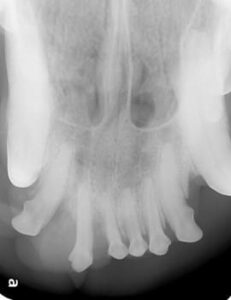

Diagnostic testing will start with a thorough oral examination and periodontal probing, dental X-rays, and computed tomography (conventional or cone beam computer tomography=CBCT). In rare cases, an MRI may be recommended.ย

Images of an oral tumor before surgery.

ย ย ย ย